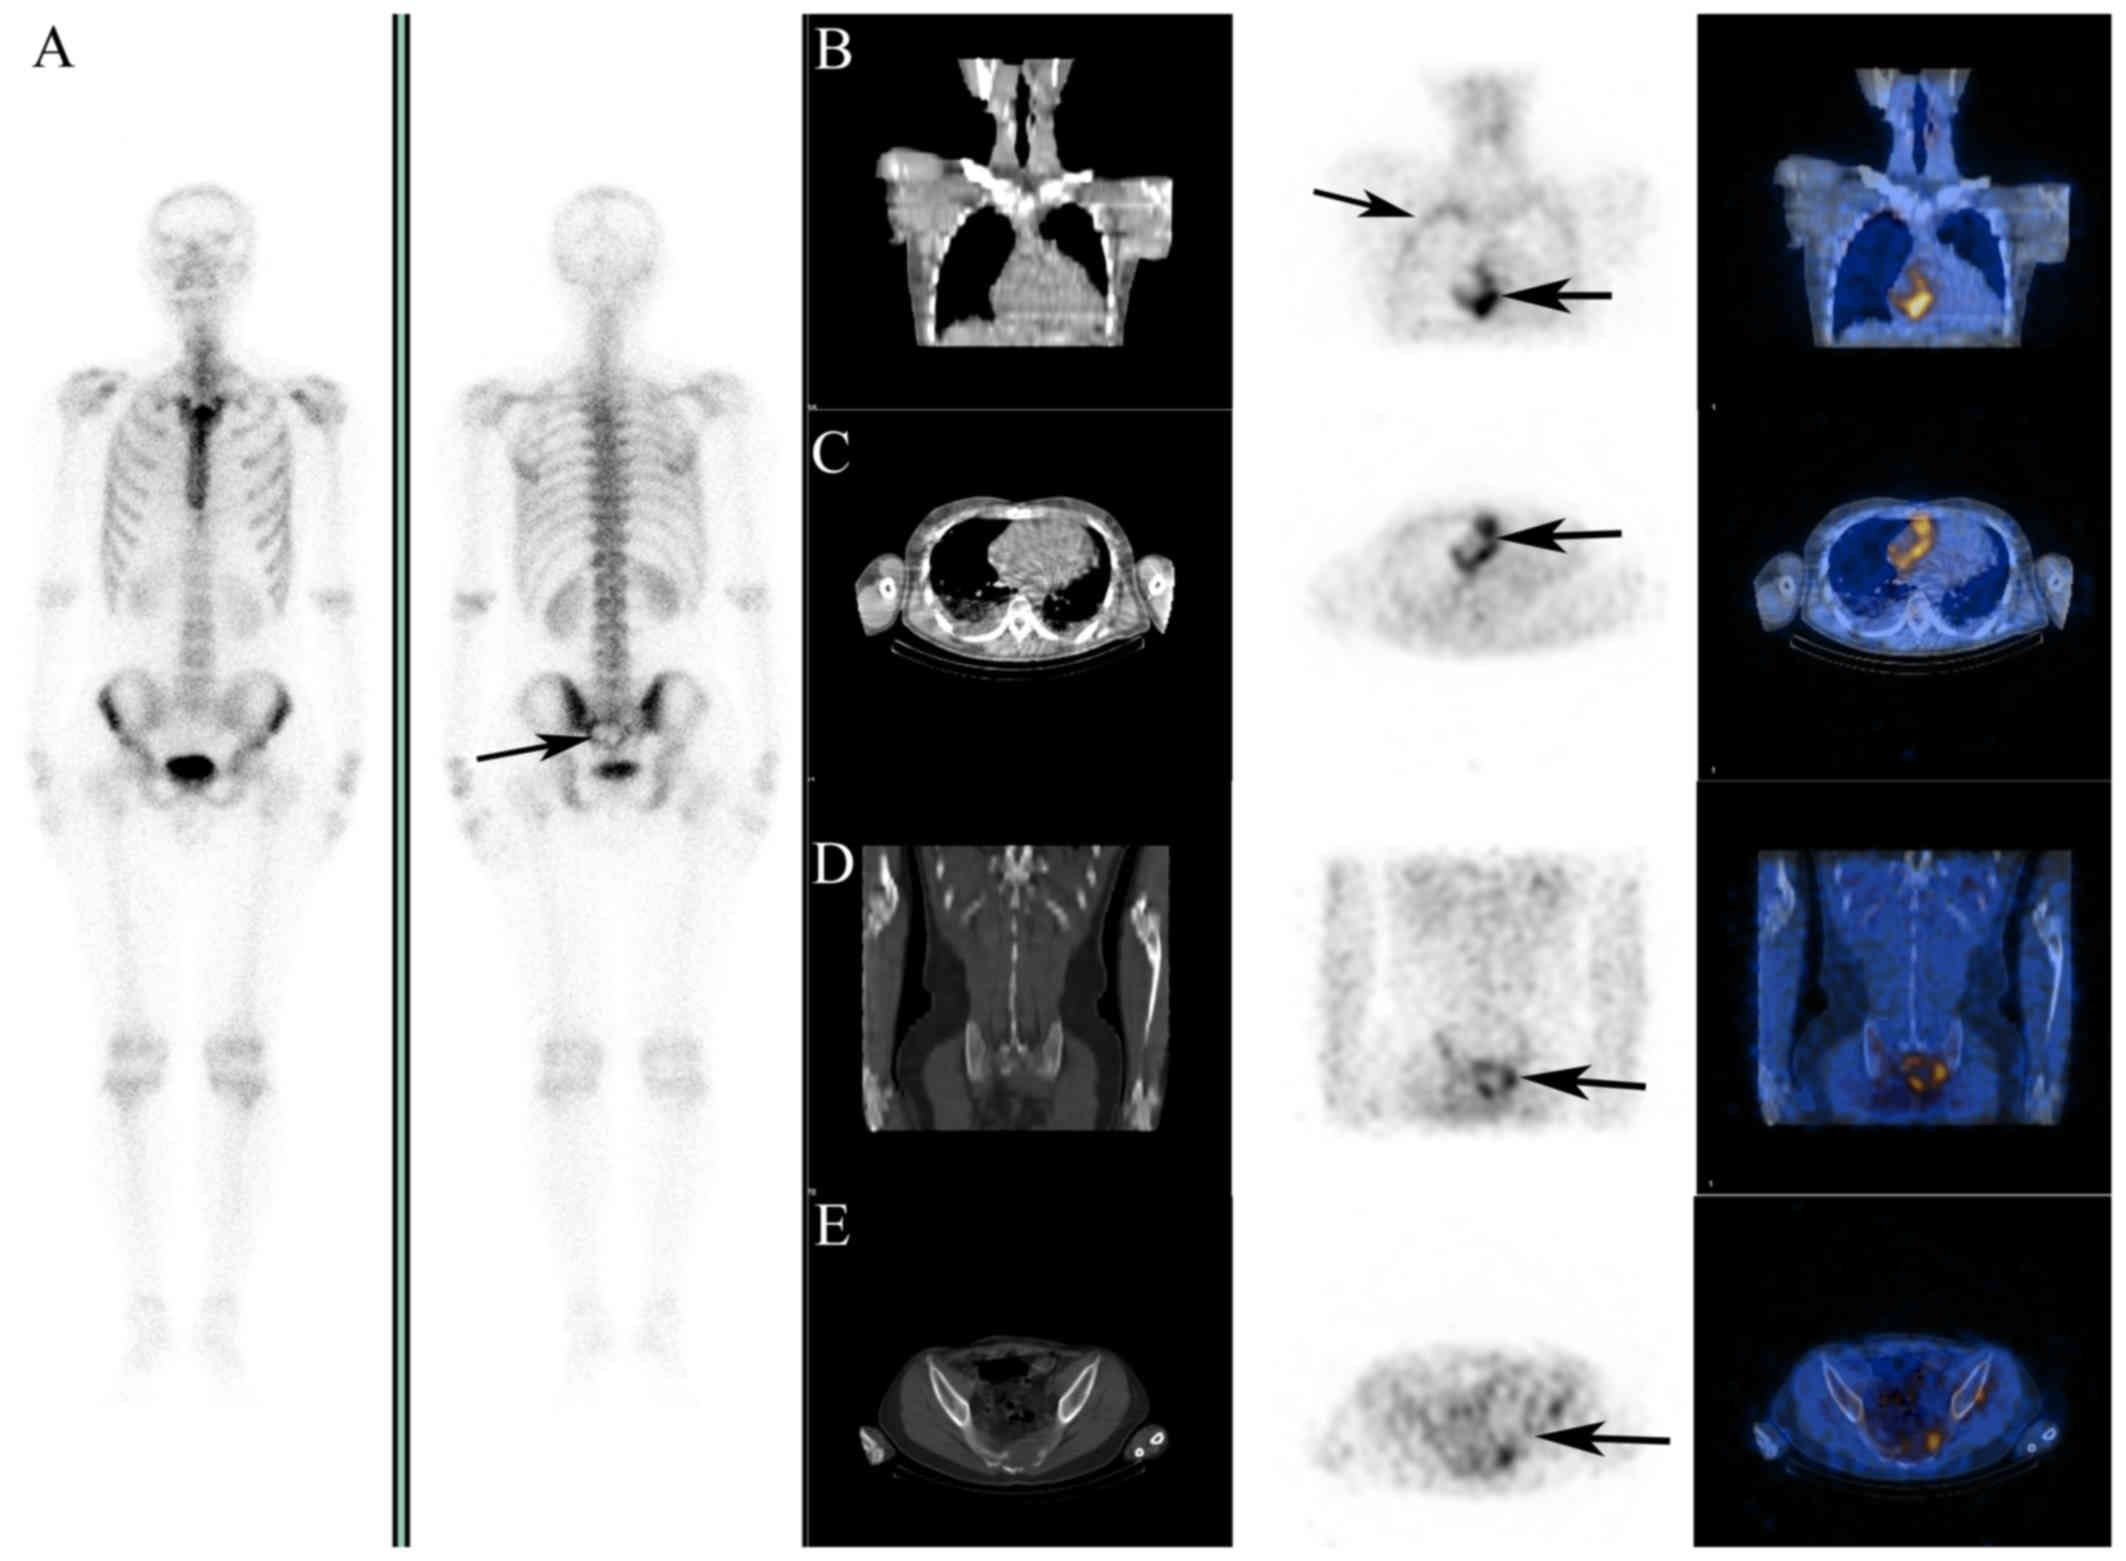

In May 2010, a 28-year-old man was admitted to the Nanjing First Hospital due to progressive left-sided chest pain and breathlessness for 4 months, which had worsened over the last 1 h. The patient had a 10-year history of smoking (1 pack/day). There was no history of tuberculosis or asbestos exposure. Two months prior to admission, the patient had been hospitalized with the same symptoms in another hospital. Physical examination, chest radiography, computed tomography (CT) and enhanced CT revealed widening of the myocardial boundary, concurrent large pericardial effusion and little-to-moderate pleural effusion (Fig. 1B). A total of 1,800 ml of pericardial fluid were evacuated. Cytological examination of the pericardial fluid only found reactive mesothelial cells, without acid-fast bacilli or tumor cells. Echocardiography revealed thickening of the free wall of the right ventricle (RV), with adhesions to the adjacent pericardium and uneven thickening of the right atrium (RA) to 0.8–1.4 cm. The thickened pericardium near the output of the RV has also restricting myocardial motion. A liquid anechoic area was detected in the pericardial cavity and pericarditis was highly suspected (Fig. 1A). Experimental antituberculosis treatment was refused when the Mantoux test was found to be strongly positive. The patient was referred to our hospital due to worsening shortness of breath and was tentatively treated with antituberculotic agents (isoniazid and rifampin), with a poor therapeutic effect and increasing volume of the pericardial effusion. 18F-FDG imaging was performed to rule out malignancy; it revealed highly increased uptake of 18F-FDG in the RA, the pericardium adjacent to the RV and RA (Fig. 2B and C, arrows), and mildly increased uptake along the inner thoracic wall (Fig. 2B, arrows). Ring-shaped radioactivity aggregation and bone destruction in the sacrum were visualized on 18F-FDG imaging (Fig. 2D and E, arrow) and 99mTc-methyl diphosphonate (MDP) whole-body scan (Fig. 2A, arrow). PMPM with RA infiltration and bone metastasis was highly suspected. An incisional pericardial biopsy was performed and pathological examination of the samples obtained by biopsy confirmed the diagnosis of PMPM with atrial infiltration (Fig. 3A) (cytokeratin5/6+, D2-40+, calretinin+, carcinoembryonic antigen−, thyroid transcription factor 1−). Following surgery, a doublet chemotherapy regimen (pemetrexed 500 mg/m2 + cisplatin 75 mg/m2 were administered on the first day of each 3-week cycle, for a total of six cycles) was introduced immediately after definitive diagnosis. During follow-up, CT imaging revealed little pericardial effusion at 4 months postoperatively (Fig. 3B), but lung metastasis and large pleural effusion were observed 1 year after the operation (Fig. 3C). The patient survived for >1.5 years after the diagnosis and succumbed to severe pericardial effusion and cardiac tamponade in September 2012.

Figure 2.

18F-FDG images and 99mTc-MDP bone scan images. (A) 99mTc-MDP whole-body scan showing a sacral osteolytic metastasis (arrow) (left, anterior view; right, posterior view). (B and C) Highly increased uptake of 18F-FDG was observed in the right atrium and the pericardium adjacent to the right ventricle and atrium, with mild increase in the inner wall of the thoracic cavity (arrows). (D and E) Ring-shaped radioactivity aggregation and osteolytic bone metastasis in the sacrum were visualized on 18F-FDG coincidence imaging (arrows). B-E: Left panel, CT; middle panel, 18F-FDG PET; and right panel, PET-CT fusion images. FDG, fluorodeoxyglucose; MDP, methyl diphosphonate; CT, computed tomography; PET, positron emission tomography.